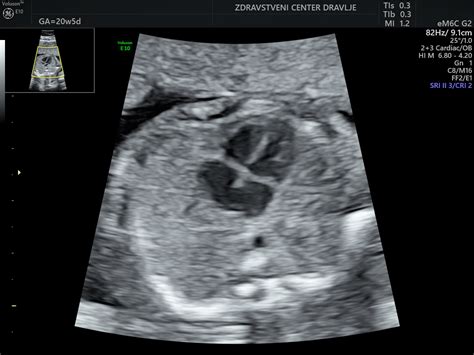

Na ultrazvoku je jasno vidno, v kakšnem položaju otrok spi v maternici. V 21. tednu nosečnosti so otrokove spalne navade in ritem povsem enaki, kot bodo ob rojstvu, na njih pa že vplivata hrup in svetloba. V tem tednu se razvija tudi otrokova mimika. Plodovnico, ki jo pogoltne, zdaj lahko predela, saj njegov prebavni sistem vodo loči od drugih prisotnih snovi. Otrok se premika in tako aktivno uri svoj prebavni sistem, čeprav črevesje še ni popolnoma razvito in bo vse, kar otrok poje, lahko prebavilo šele, ko bo otrok star približno 12 mesecev. Otrokov okušalni živec in brbončice so zdaj razviti že do te mere, da otrok lahko okusi, kaj jeste vi, okusi vaše hrane namreč pridejo v plodovnico, ki jo otrok nato zaužije. Kasneje bo otrok te okuse prepoznal, ko bo videl hrano na svojem krožniku.

Vaš otročiček v 21. tednu nosečnosti tehta približno 350 g in je zdaj že težji od posteljice. Prebavni sistem vašega otroka že deluje, četudi na poenostavljen način. K razvoju prebavnega sistema pripomore tudi požiranje plodovnice, ki je hkrati tudi vir hranil za otroka. Ob ultrazvočnem pregledu je zdaj mogoče videti številne otrokove dejavnosti, vključno s požiranjem in sesanjem palca. Omega 3 in 6 maščobne kisline sta dve skupini maščobnih kislin, med katere sodijo tudi dolgoverižne polinenasičene maščobne kisline (znane pod skupnim imenom LCP). Ena od omega 3 maščobnih kislin LCP se imenuje dokozaheksaenojska kislina ali krajše DHA. Med nosečnostjo DHA prispeva k razvoju otrokovih možganov, podpira pa tudi razvoj njegovih oči.